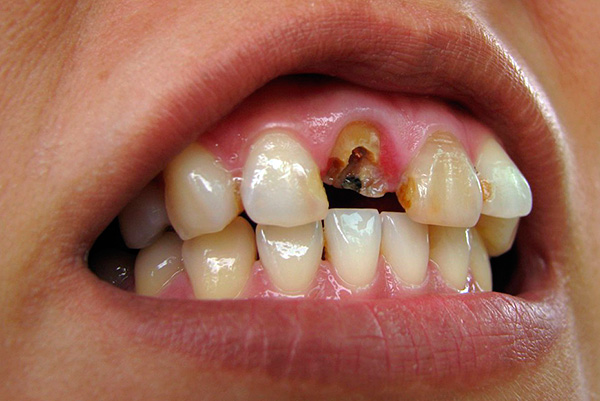

- Destruição completa da coroa dentária quando é impossível usar a raiz para fins ortopédicos;

Então, o que é importante ter em mente: a odontologia moderna há muito tempo ultrapassa esses preconceitos. Agora, não apenas com cárie (mesmo profunda) e pulpite, mas com a maioria das periodontites, os dentes são tratados notavelmente e não precisam ser apressados para remover. E mesmo que o dente, ao que parece, tenha se rompido sob a raiz, não é fato que a raiz precise ser removida, pois é bem possível restaurar a funcionalidade e estética do dente usando a aba e a coroa da raiz.